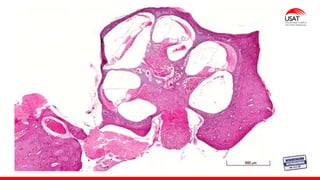

La cóclea es un tubo ligeramente cónico

enrollado sobre sí mismo en 2 1/2 vueltas,

de aspecto muy similar al de un caracol,

su longitud total aproximadamente es de

32 - 35 mm.

COCLEA